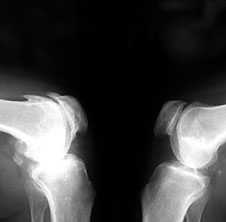

Рис. 2. Rо-графия коленных суставов в боковой проекции.

Артроз феморопателлярных суставов (больше слева). Артроз коленных суставов (I ст по Kollgren справа, IV ст. по Kollgren слева)

Ранние рентгенологические признаки (соответствуют 1-2 стадиям артроза по Kellgren):

1. Вытягивание и заострение краев межмыщелкового возвышения большеберцовой кости (в месте прикрепления крестообразной связки).

2. Небольшое сужение суставной щели (чаще в медиальном отделе сустава).

3. Заострение краев суставных поверхностей мыщелков бедренной и большеберцовой кости, чаще в медиальном отделе сустава (связано с большей нагрузкой на этот отдел сустава), особенно при наличии варусной деформации сустава; реже - в латеральной части или одновременно в обеих половинах суставной поверхности (рис. 2).

При прогрессировании артроза коленных суставов (соответствует 3-4 стадиям артроза по Kellgren):

• нарастает сужение суставной щели

• развивается субхондральный остеосклероз в наиболее нагруженной части сустава

• появляются множественные крупные остеофиты на боковых, передних и задних краях суставных поверхностей

• редко обнаруживаются субхондральные кисты